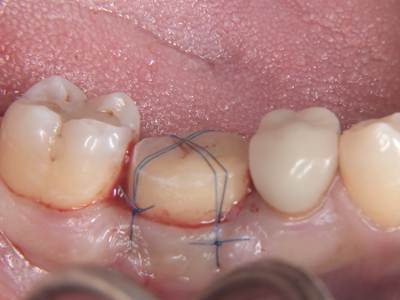

術後評価(咬合・適合良好):症例1-7

術後評価(咬合・適合良好)